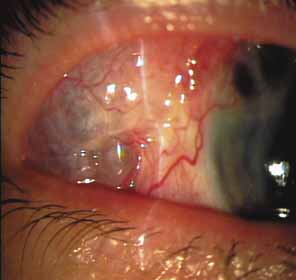

The possible association between retinitis pigmentosa and glaucoma dates back to 1862.11 Over the past century the reported glaucoma incidence has varied between 2.98% to 10% of all cases of retinitis pigmentosa.12,13 Of concern in all previous reports is the accuracy of the diagnosis of retinitis pigmentosa itself, a hereditary disease with diverse manifestations. Retinitis pigmentosa-like syndromes may mimic glaucomatous field loss, and the pattern of advancement of visual field loss in true retinitis pigmentosa may parallel that of typical open-angle glaucoma. Patients with undiagnosed retinitis pigmentosa may have subtle fundus findings, especially those with the sine pigmento form (Fig. 1). A clue to diagnosis is the disproportionate peripheral field loss in comparison to the degree of optic nerve cupping and rim pallor. Patients with atypical field loss and minimal optic nerve cupping should have an electroretinogram to exclude unsuspected retinitis pigmentosa.

The majority of cases of ghost cell glaucoma occur following vitrectomy for diabetic retinopathy, vitreous hemorrhage due to trauma, or vitreous hemorrhage following anterior segment surgery (i.e., cataract extraction or corneal transplant). Although studies suggest that a disruption of the anterior hyaloid face may be a necessary precedent, ghost cell glaucoma probably can occur with an intact hyaloid if a sufficient quantity of vitreous blood is present.27 The clinical presentation includes acute pressure elevation, corneal edema, and lack of keratic precipitates. Minute tan cells (ghost cells) may layer out, producing a pseudohypopyon or, if admixed with blood, a “candy-striped” hypopyon. (Fig. 3) Intraocular pressure elevations after diabetic vitrectomy raise concerns regarding concomitant neovascular glaucoma. However, neovascular glaucoma rarely develops in the immediate postvitrectomy period, unless some anterior segment neovascularization was present preoperatively. Late-onset pressure elevations (> 6 to 8 weeks out) in a postvitrectomized diabetic eye usually signal neovascular glaucoma.

Both benign and malignant tumors can produce a secondary glaucoma. Shields and associates29 found 5% (126) of 2,704 eyes diagnosed with intraocular tumors suffered glaucoma. The glaucoma rate was only 2% in eyes with choroidal melanomas but rose to 17% in eyes with melanomas of the ciliary body.28 The mechanism of glaucoma in posterior segment melanomas was usually iris neovascularization (Fig. 4; Table 3).30 The incidence of glaucoma in tumor-containing eyes was found to rise when retinal detachment was present. In eyes presenting with reduced vision, glaucoma, opaque media, and an uncertain history of visual loss, it is prudent to exclude an unsuspected neoplasm by performing diagnostic B-scan ultrasonography.